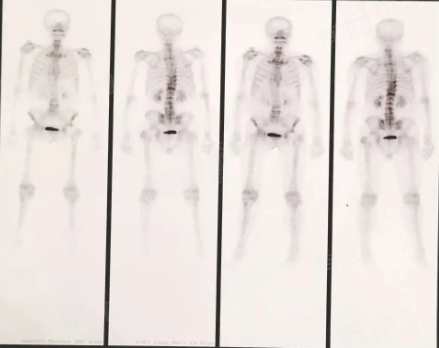

骨扫描后通常在2-3天后可以接触孩子。骨扫描是一种常见的医学检查手段,利用放射性核素对骨骼进行成像,以帮助医生诊断各种骨骼疾病和肿瘤等情况。